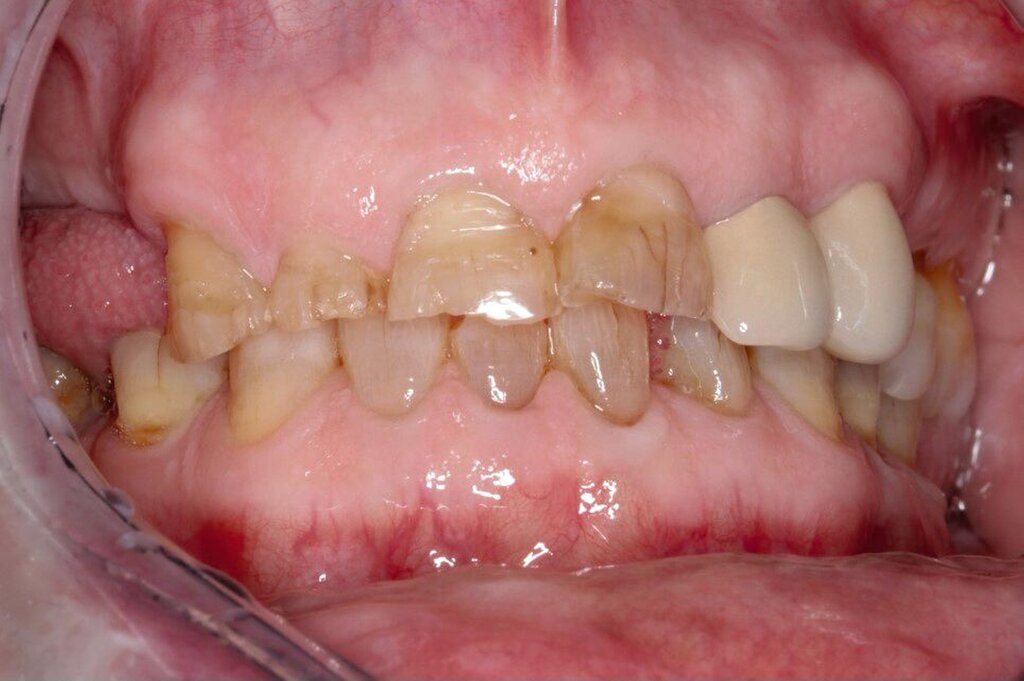

Zahnärztlich werden Hypophosphatasie-assoziierte Befunde häufig als eine rasch progrediente Parodontitis, eine atypische Kariesanfälligkeit, MIH oder schlicht als Folge „schlechter Mundhygiene“ fehlinterpretiert. Typisch für Hypophosphatasie ist jedoch eine strukturell bedingte parodontale Instabilität bei im Verhältnis oft geringer oder inkonsistenter Entzündung – das passt initial häufig nicht zu einem klassischen parodontalen Krankheitsbild und erklärt daher viele dieser Fehlzuordnungen.

Klinisch besonders charakteristisch ist eine atraumatische Zahnlockerung, teils sogar bei wirklich guter Mundhygiene. Zahnverluste können auftreten, obwohl die parodontale Entzündung disproportioniert gering ist – also ohne „ersichtliche“ klassische entzündliche Ursache. Parodontal zeigen sich häufig erhöhte Sondierungstiefen und Attachmentverlust; gleichzeitig müssen typische gingivale oder parodontale Entzündungszeichen im Initialstadium nicht zwingend auffällig sein. Genau diese Kombination – Lockerung plus wenig Entzündung – sollte sofort hellhörig machen.

Beikler: Ja, die gibt es – und diagnostisch ist das sehr wertvoll, weil es erklärt, warum die klinischen Befunde oft nicht zur Entzündungslogik passen. An den Zahnhartsubstanzen sieht man häufig eine Hypomineralisation des Schmelzes, teils mit hypoplastischen Schmelzformen. Klinisch auffällig ist auch eine deutlich erhöhte Schmelz-Transluzenz, was dazu führt, dass die Zähne dunkler aussehen. Seltener ist auch das Dentin betroffen: Es kann hypomineralisiert sein, oft mit vergrößerten Pulpakammern.

Besonders charakteristisch sind Veränderungen am Wurzelzement: Häufig finden sich zementarme oder zementfreie Wurzeloberflächen, histologisch nicht selten eine ausgeprägte Hypoplasie bis Aplasie des azellulären Zements. Dadurch können die Sharpey-Fasern nicht ausreichend inserieren – die Verankerung ist strukturell geschwächt, ohne dass primär eine ausgeprägte Entzündung vorliegen muss. Auch der Alveolarknochen ist oft hypomineralisiert, was die Stabilität zusätzlich beeinträchtigen kann. In der Praxis ist diese Konstellation insbesondere dann diagnostisch wegweisend, wenn sie mit frühem Zahnverlust beziehungsweise auffälliger Lockerung einhergeht.

Gegenüber einer rasch progredienten Parodontitis (Grad C) oder dem Papillon-Lefèvre-Syndrom ist entscheidend, dass diese Krankheitsbilder meist durch eine ausgeprägte Entzündung und Plaque sowie tiefgreifende Attachmentverluste geprägt sind. Bei Hypophosphatasie sind diese Entzündungszeichen häufig nicht proportional zu dem, was man klinisch an Lockerung und Attachmentverlust sieht. Der wichtigste praktische Marker ist daher: atraumatischer Zahnverlust beziehungsweise ausgeprägte Zahnlockerung bei primär wenig Entzündung – häufig schon im Milchgebiss – in Kombination mit muskuloskelettalen Beschwerden, Stressfrakturen oder einer entsprechenden Familienanamnese.